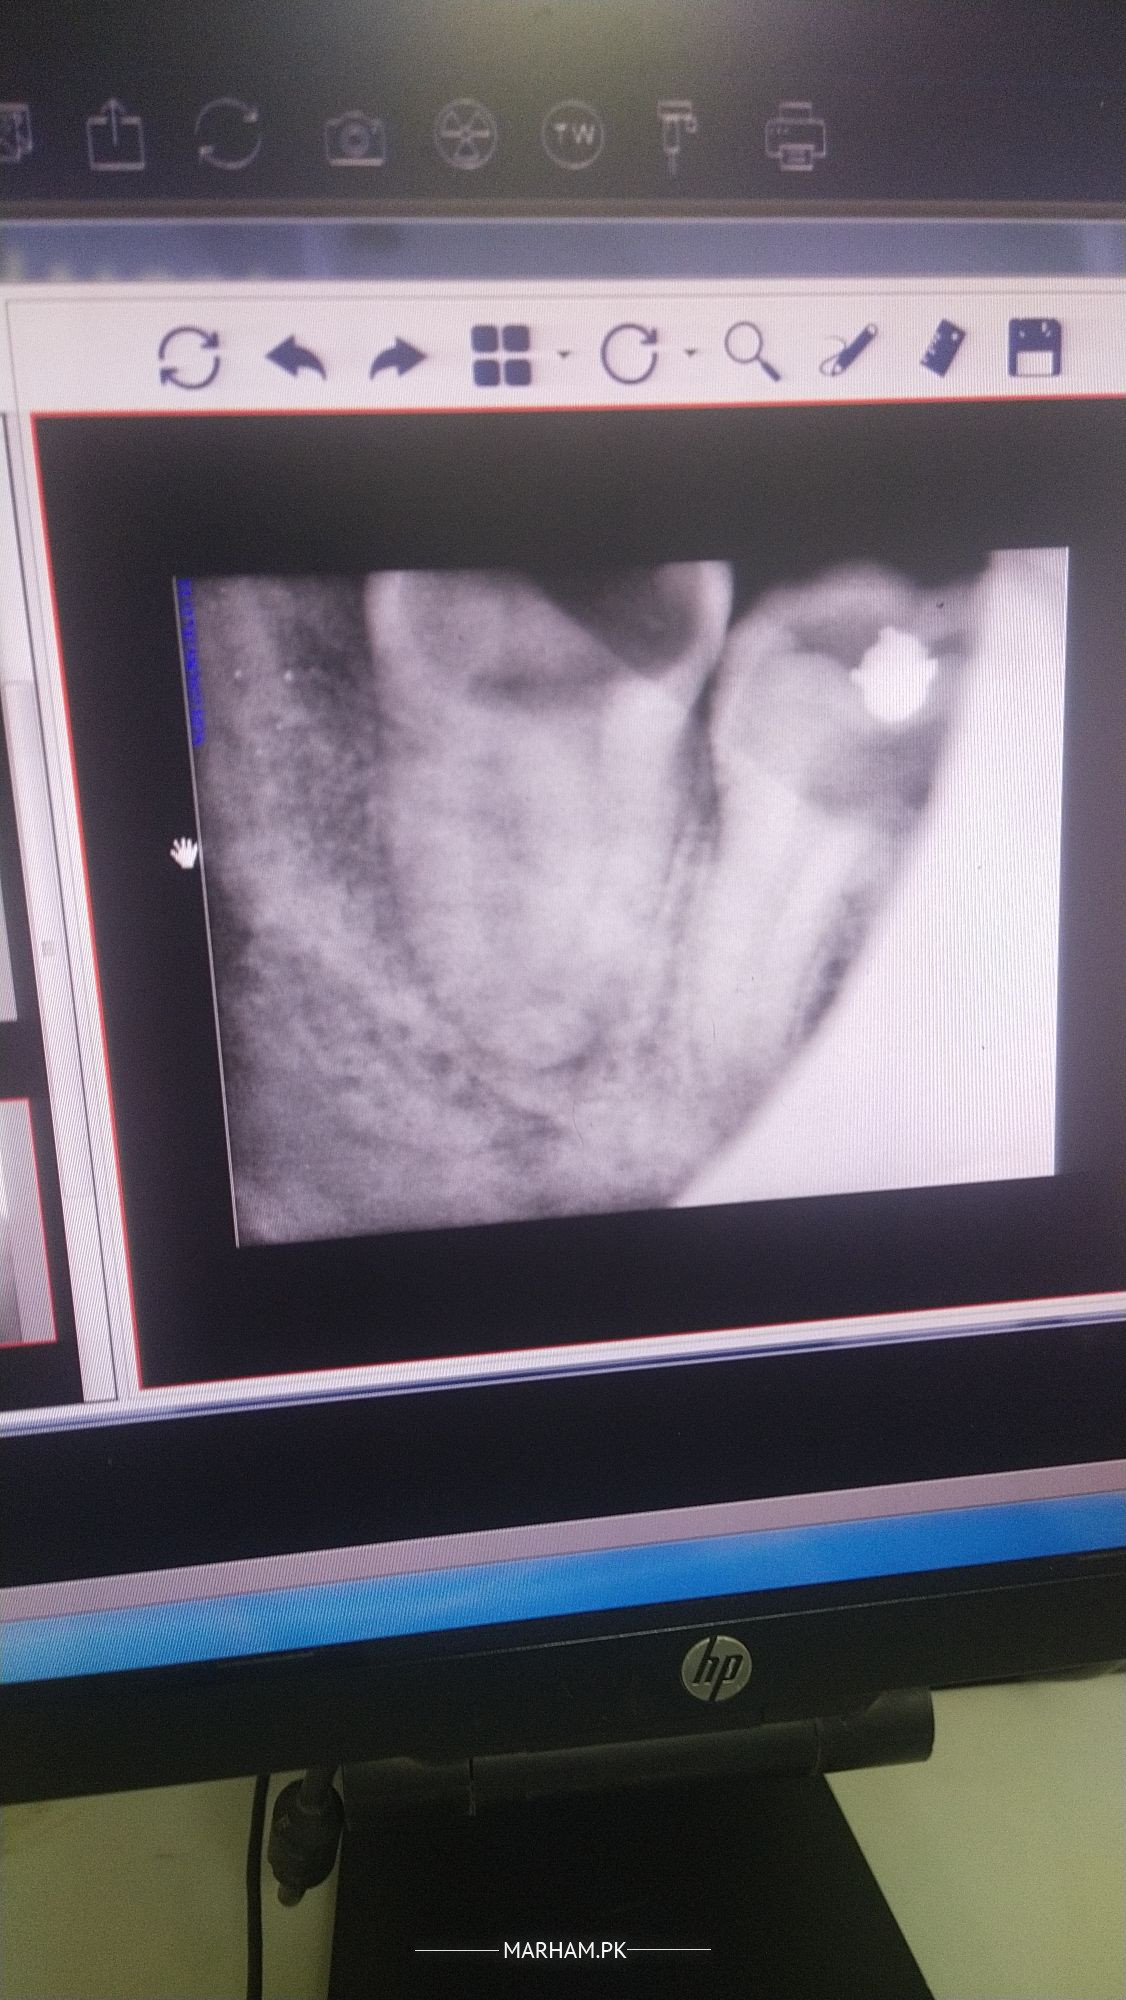

want to know wisdom tooth extraction through simple procedure or through surgery? X -ray attached here

Clinical examination is must to reach final approach, although xrays suggests surgical extraction.

by radiograph extraction is simple one

It is grossly carious and root is curved so it could be surgical. Clinical examination is also important.

Hey for a correct procedure choice it is important to examine clinically too. The x ray is also not that clear but from this picture it looks like partially in bone. It will require surgical extraction. Let the dentist who is performing the procedure decide what's best.

surgical extraction recommended

A surgical extraction is needed.

Clinical examination is required. Although Xray suggests surgical extraction as tooth is grossly carious.

complete evaluation req. visit dentist. I prefer surgical ext

nonsurgical (simple )is expected .

but surgery may be needed.